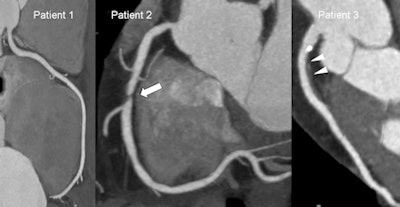

| Images show coronary CT angiograms of three different patients of similar age and with similar risk factor profiles. Images were acquired with a dual-source CT system (Siemens Flash; radiation dose <1.5 mSv for each patient). Patient 1 has normal coronary arteries. Patient 2 has a significant coronary stenosis in the absence of coronary calcifications (arrow). Patient 3 has a large soft plaque (arrowheads) and smaller calcified plaques in the absence of luminal narrowing. According to a recent meta-analysis by Bamberg et al, patients 2 and 3 have an increased risk of future cardiovascular events compared to patient 1, despite similarities of age and risk factor profile. Hazard ratio for patient 2 = 10.7; hazard ratio for patient 3 = 4.5. (Provided by Dr. Fabian Bamberg) |

Lowered radiation dose means that CT angiography (CTA) has become far more acceptable in intermediate-risk patients for assessing the future risk of a major cardiac event, such as myocardial infarction or the need of coronary stenting. CTA used to involve a dose of 10 to 20 mSv, but with the latest scanners, half of patients examined receive less than 1 mSv. Even scanners released in the past five years usually involve a dose of only 3 to 8 mSv. In addition, a recent meta-analysis has shown that the presence of ≥ 1 significant coronary stenosis was associated with an annualized event rate of 11.9%, with a corresponding hazard ratio of 10.74, demonstrating that coronary CTA can be used to identify patients at risk for cardiovascular events.